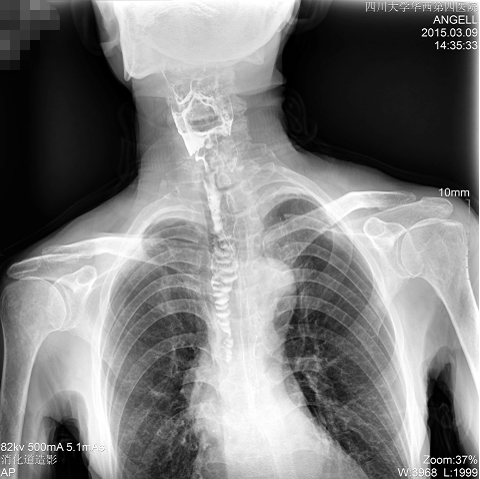

如下圖所示:該患者因吞咽時(shí)感到很難受,進(jìn)食時(shí)也經(jīng)常咳嗽故就醫(yī)診斷。華西醫(yī)院醫(yī)生使用動(dòng)態(tài)DR為病人進(jìn)行消化道造影診斷,要求他吞鋇后發(fā)現(xiàn),食道各段通過(guò)順利,形態(tài)規(guī)則,雙側(cè)梨狀窩不對(duì)稱左側(cè)稍淺,多次吞咽動(dòng)作后,仍見鋇劑滯留,并見鋇劑進(jìn)入氣管,屬于會(huì)厭征陽(yáng)性。會(huì)厭功能紊亂,鋇劑進(jìn)入了氣管。

圖為正位:通過(guò)動(dòng)態(tài)影像可以清楚看到鋇劑進(jìn)入了支氣管道且雙側(cè)梨狀窩不對(duì)稱